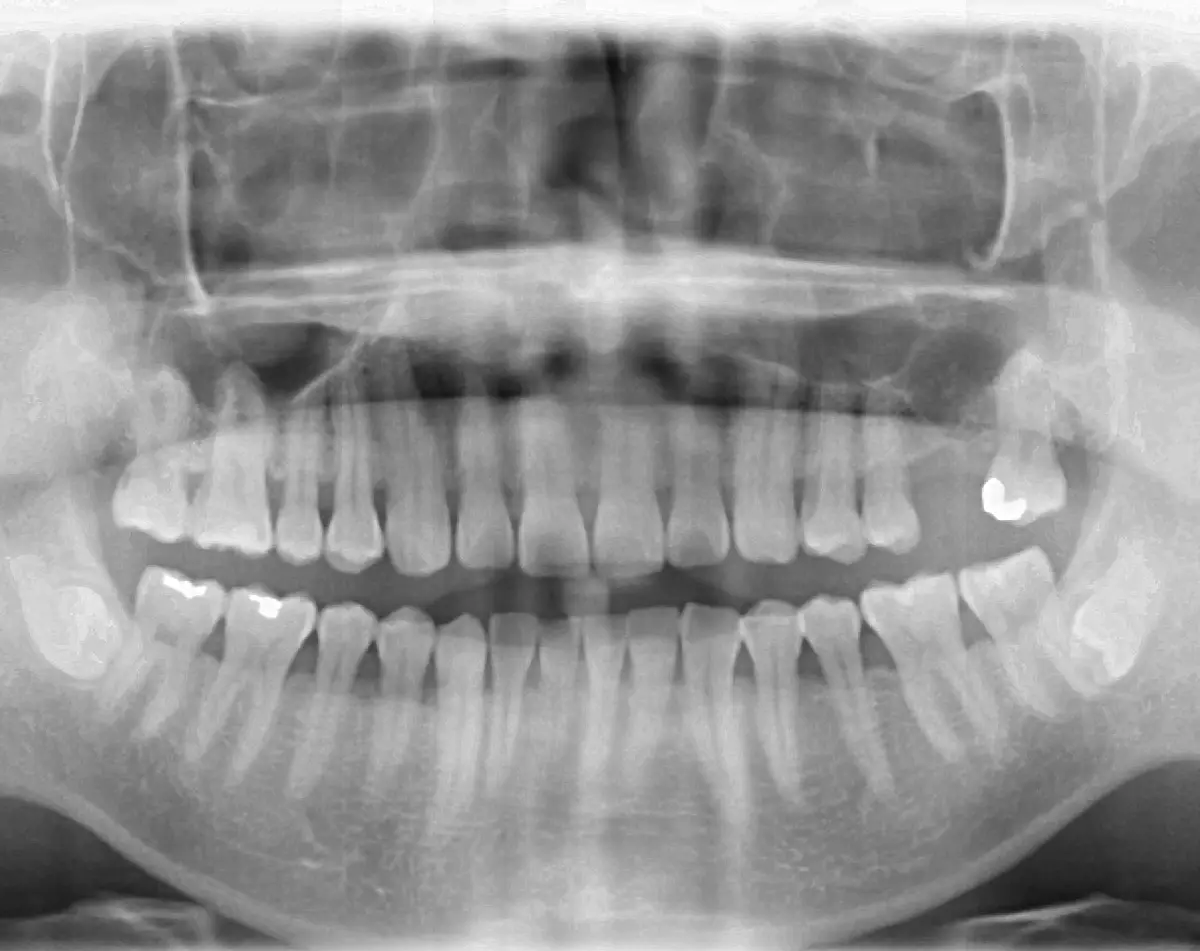

4D Full Mouth Rehabilitation

before

after